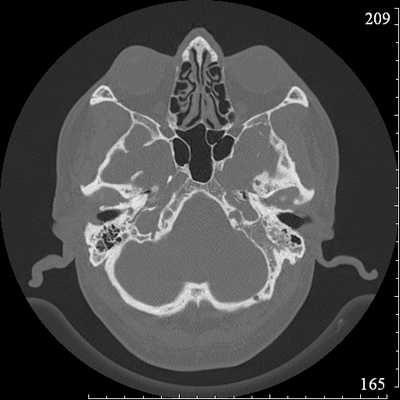

КТ основана на применении компьютерных алгоритмов для построения изображений из отдельных «срезов». Первые аппараты КТ назывались «аппаратами компьютерной аксиальной томографии» (КАТ), потому что они могли строить изображения только в аксиальной плоскости. Современные аппараты могут собирать большой массив данных и строить из него изображения в любой плоскости, в том числе трехмерные.

КТ позволяет детально оценить костную структуру височной кости. (С этого места и далее будет подразумеваться, что КТ анализируется в режиме «костного окна», т.е. контраст и яркость выставлены таким образом, что бы обеспечить наилучшую визуализацию костных тканей; все мягкие ткани будут иметь насыщенный серый цвет). Этот режим отличается от «мягкотканного окна», в котором разные мягкие ткани на снимках представлены как разные оттенки серого. В мягкотканном окне костная ткань выглядит слишком яркой, из-за чего точно визуализировать архитектуру кости становится невозможным.

На КТ все кости и структуры с высоким содержанием кальция имеют белый цвет, воздух — черный, а мягкие ткани — серый.